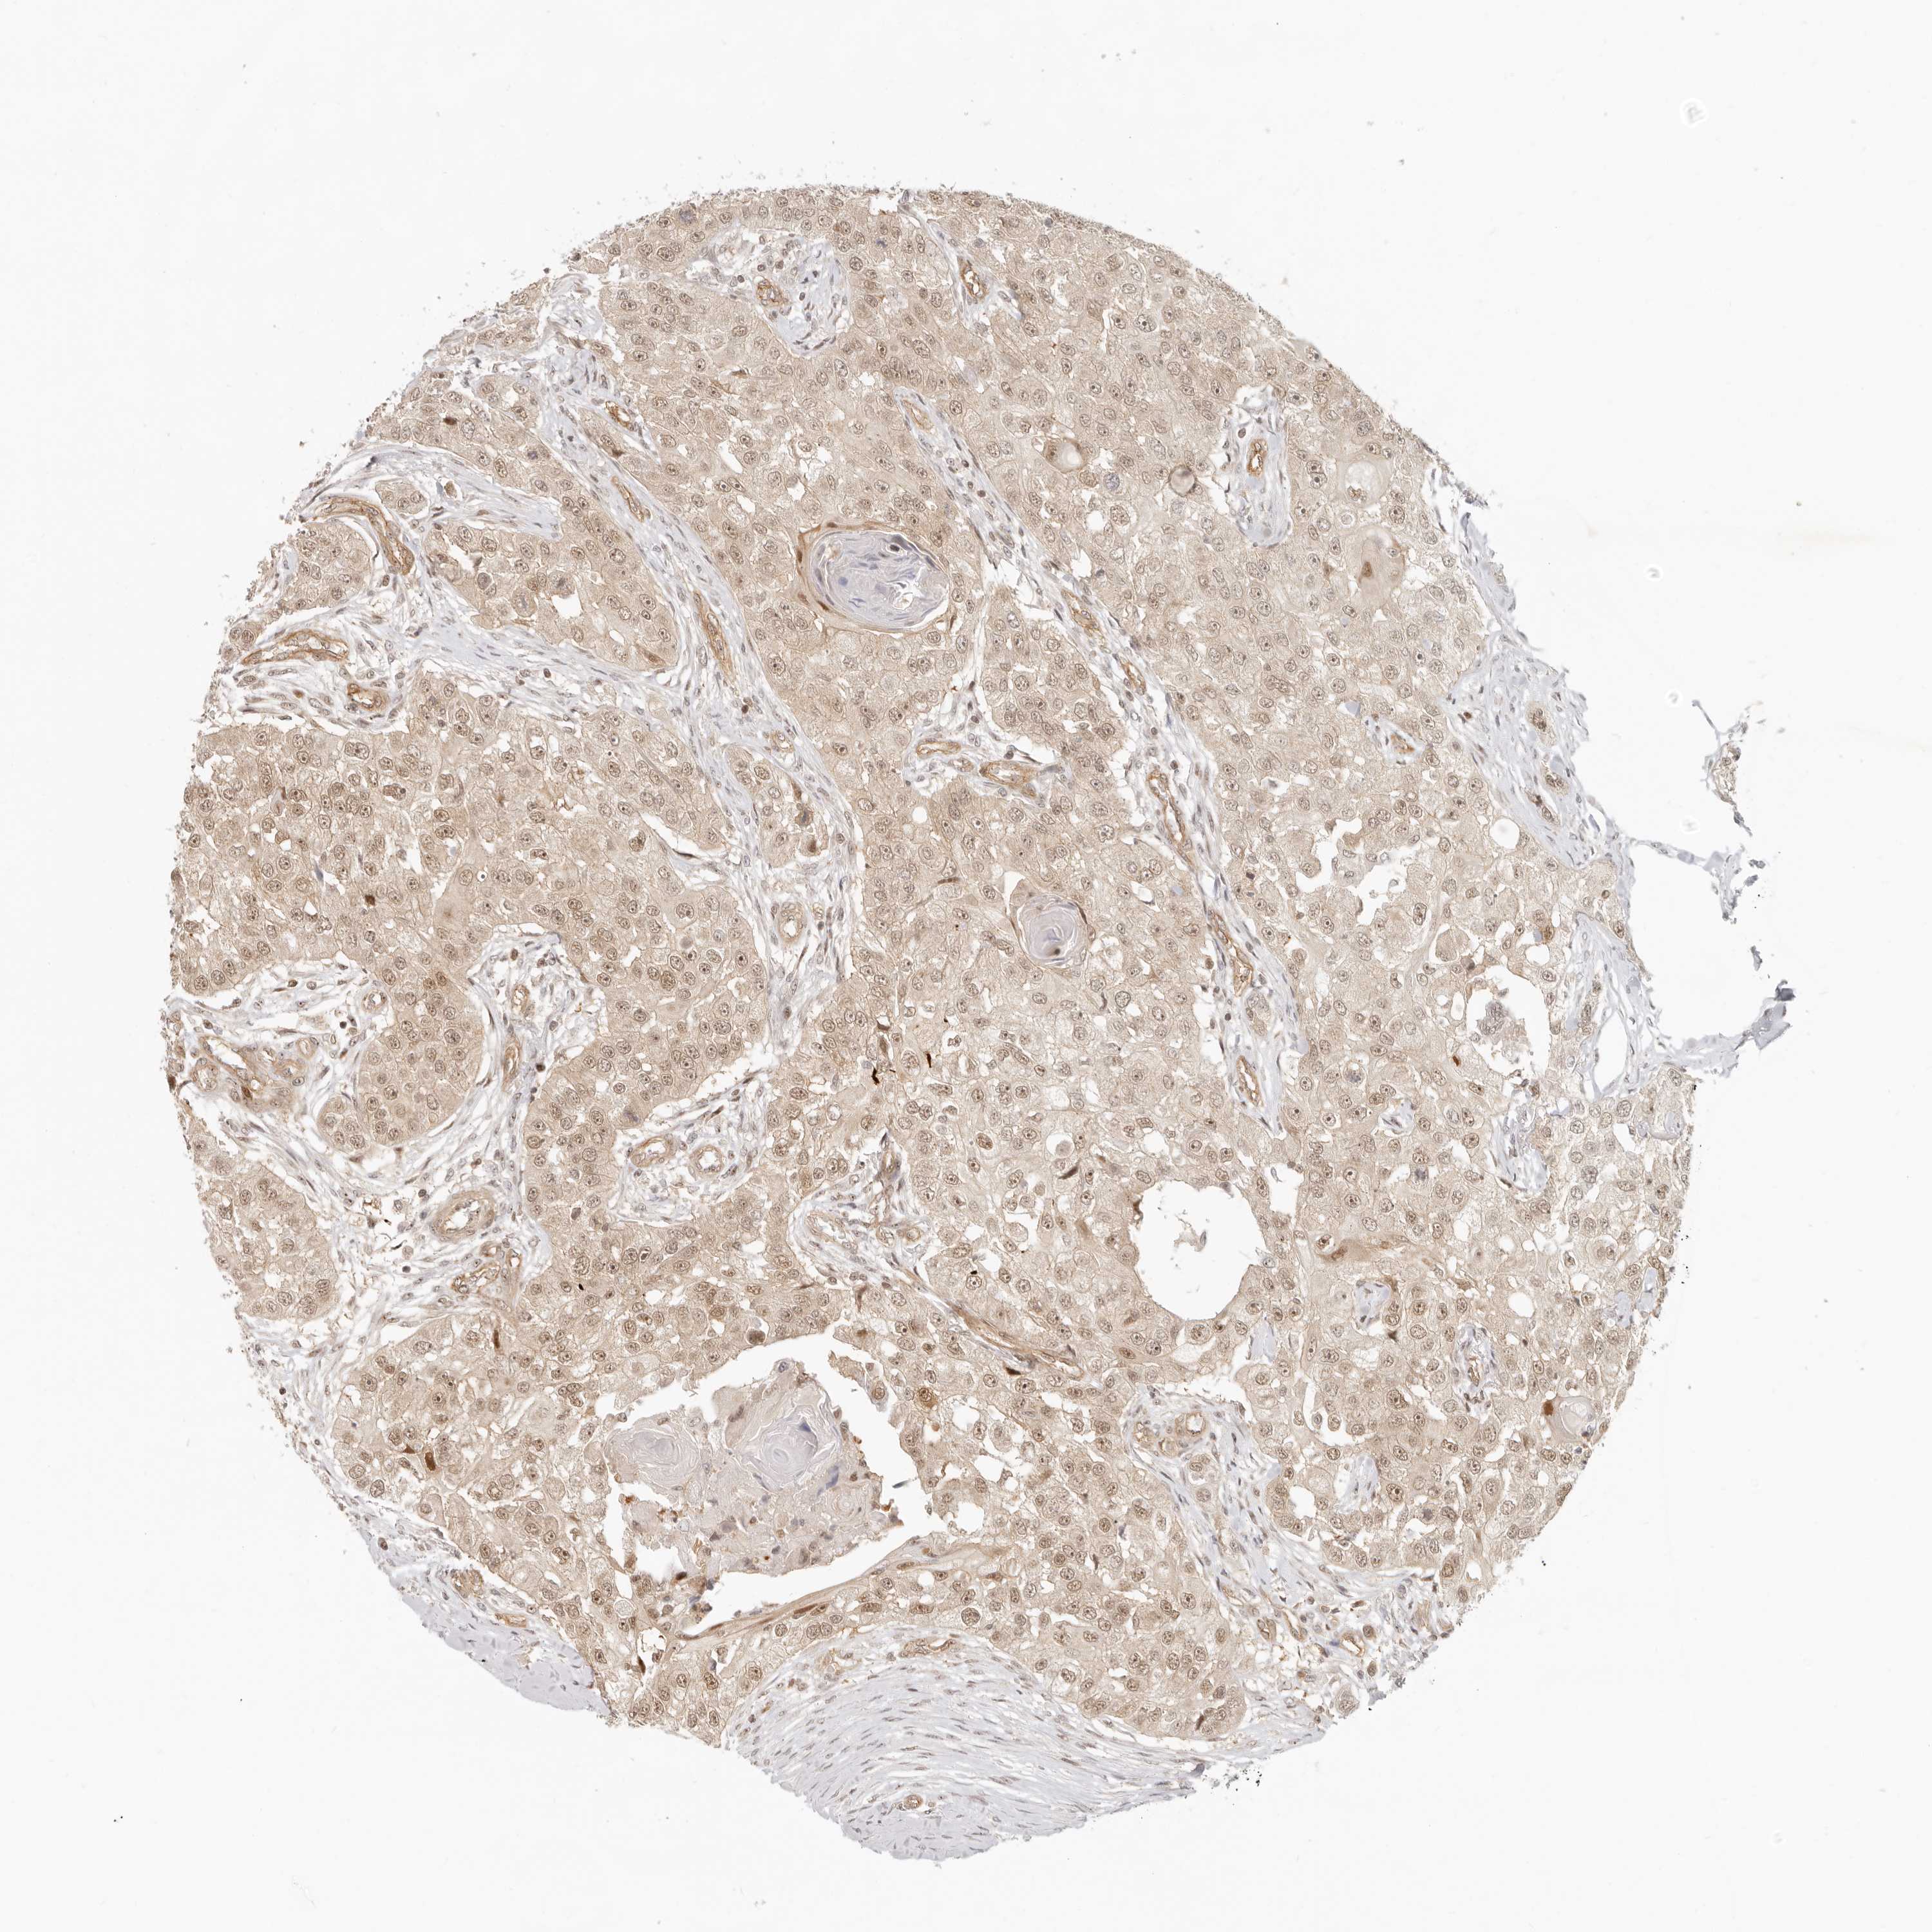

HEAD AND NECK CANCER - Protein expressioni

A mouse-over function shows sample information and annotation data. Click on an image to view it in a full screen mode. Samples can be filtered based on level of antibody staining by selecting one or several of the following categories: high, medium, low and not detected. The assay and annotation is described here.

Antibody stainingi

Antibody staining in the annotated cell types in the current human tissue is reported as not detected, low, medium, or high, based on conventional immunohistochemistry profiling in selected tissues. This score is based on the combination of the staining intensity and fraction of stained cells.

Each image is clickable and will lead to virtual microscopy that enables deeper exploration of all samples and also displays staining intensity scores, fraction scores and subcellular localization as well as patient and tissue information for each sample.

Antibody CAB004322

Squamous cell carcinoma, NOS

Squamous cell carcinoma, metastatic, NOS

Adenocarcinoma, NOS

Neoplasm, malignant, NOS